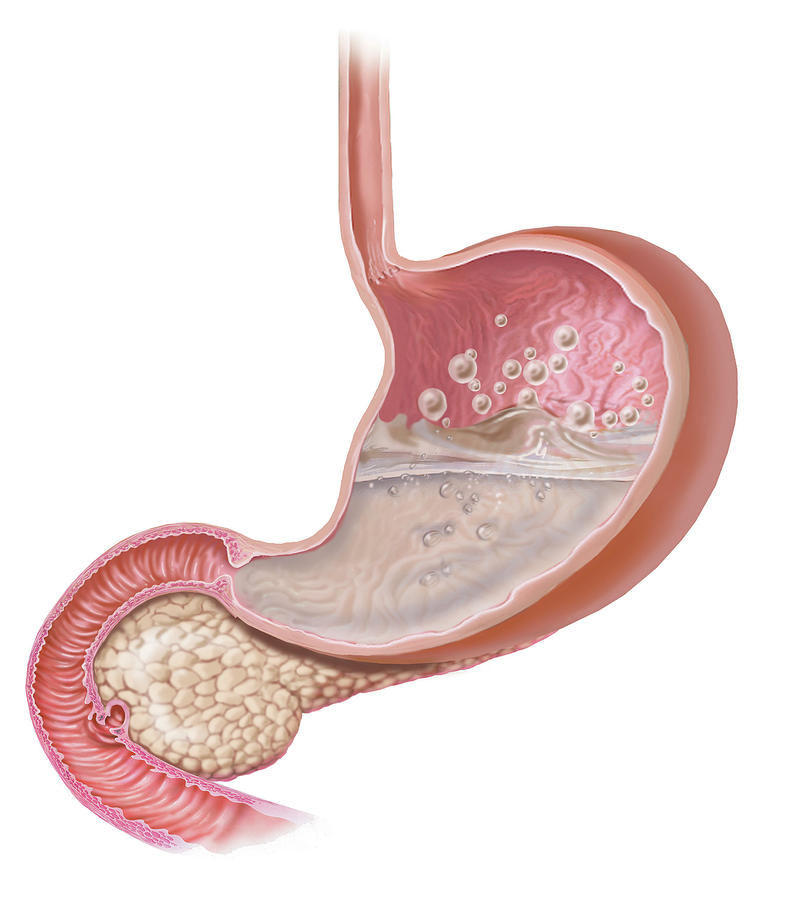

Stomach With Excessive Gas And Bubbles Photograph by Elise Walmsley Mac …

3D Illustration of the Stomach Showing the Interior Doing the Digestion …

3D Illustration of the Stomach Showing the Interior Doing the Digestion …